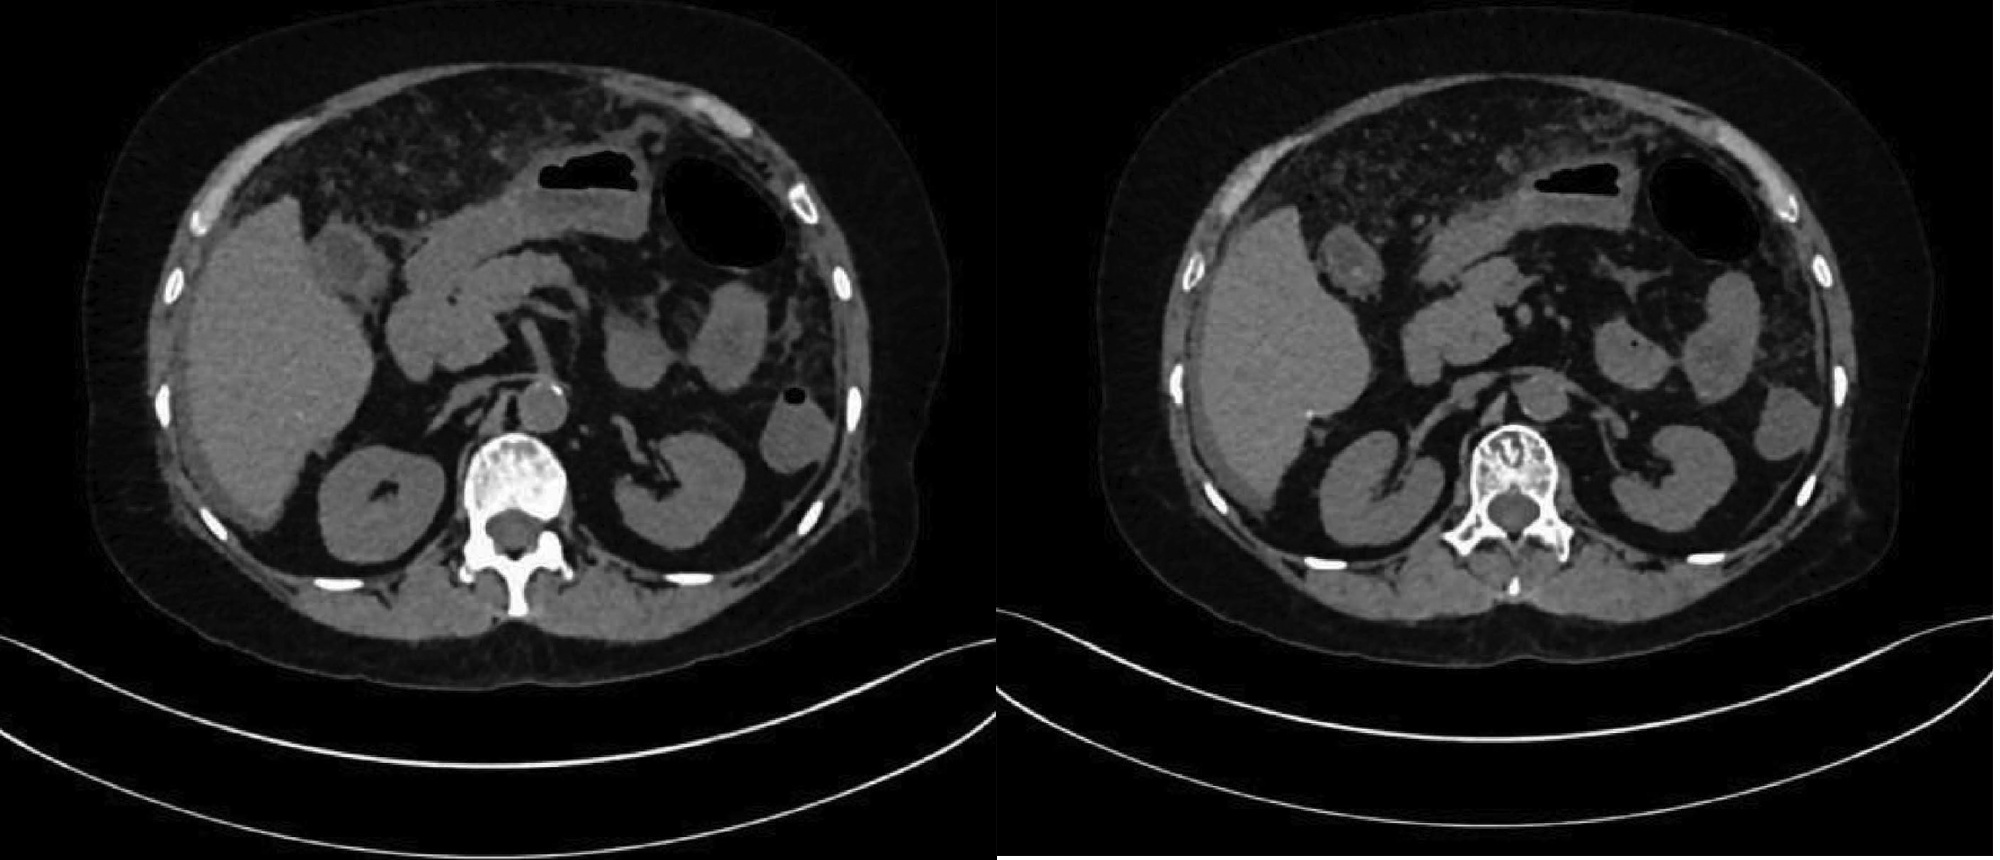

乙型肝炎肝硬化上消化道出血的ΔCT特征性表现及预测模型的建立

李俊杰, 孙岩岩, 李将宏, 郑虹

2022, 38(5): 1081-1085. DOI: 10.3969/j.issn.1001-5256.2022.05.020

摘要(1053) HTML (308) PDF (2671KB)(64)

摘要:

目的  本研究旨在寻找乙型肝炎肝硬化CT特征,建立肝硬化上消化道出血预测模型,预测出血风险。  方法  回顾性分析2015年1月—2021年6月天津市第一中心医院101例型肝炎肝硬化患者的数据,将其分为上消化道出血组(P=58)及非出血组(n=43)。比较两组间实验室检查以及强化CT检查测的平扫期、动脉期、门脉期以及静脉期的CT值,并计算各期间CT值的变化(ΔCT)。计量资料两组间的比较使用t检验或Mann-Whitney U检验;使用logistic回归分析方法,预测相关危险因素;通过计算受试者工作特征曲线下的面积评估模型辨别力,而模型校准则通过Hosmer-Lemeshow确定。在多变量logistic回归分析结果的基础上,使用Rstudio4.1.2软件的R包构建预测的列线图模型,并绘制相应的ROC曲线、校准曲线以及临床决策曲线。  结果  非出血组血清TBil、WBC、PLT水平与出血组比较,差异均有统计学意义(P值均<0.05);两组在肝-Plain、脾-P-Plain、脾-P-A ΔCT值存在统计学差异(P值均<0.05)。单因素logistic分析结果显示,白细胞(OR=0.770,95%CI:0.624~0952, P=0.016)、血小板(OR=0.979,95%CI:0.965~0.994, P=0.006)、肝脏平扫期(OR=1.142,95%CI:1.058~1.233, P=0.001)、脾脏门脉期-平扫ΔCT值(OR=0.979,95%CI:0.959~1.000, P=0.050)、脾脏门脉期-动脉期ΔCT值(OR=0.979,95%CI:0.944~0.994, P=0.015)在乙型肝炎肝硬化患者发生上消化道出血与未出血两者之间差异具有统计学意义。多因素logistic分析结果显示血小板(OR=0.968,95%CI:0.944~0.993, P=0.011)、肝脏平扫期(OR=1.148,95%CI:1.047~1.259, P=0.003)、脾脏门脉期-动脉期ΔCT值(OR=0.951,95%CI:0.908~0.995, P=0.030)为上消化道出血的独立危险因素。基于多因素logistic分析结果,构建了乙型肝炎肝硬化上消化道出血的预测模型并绘制校准曲线。该模型的受试者特征曲线下面积为0.801,cut-off值为0.433,其对应的敏感度是81.4%,特异度是77.6%。模型的校准曲线与理想曲线贴合良好。  结论  乙型肝炎肝硬化肝脏具有特殊的ΔCT变化,通过ΔCT构建的预测模型对于乙型肝炎肝硬化上消化道出血具有良好的预测能力。